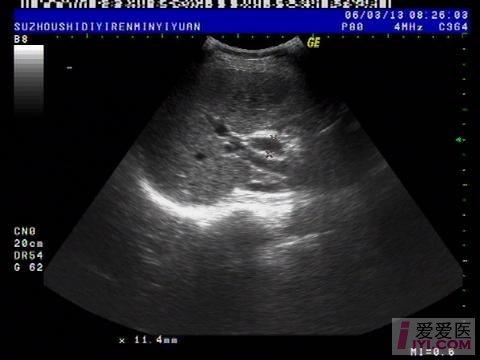

今天上午检查的一位病人, 胆囊切除术后会不会一定伴有胆总管扩张?

肝脏:左叶:长度47mm,厚度63mm 右叶:斜径106mm,形态规则,包膜完整,肝区光点细密,内部回声均匀,肝内血管走行清晰。 门静脉内径10mm。

胆囊:已切除。 胆总管:内径:11mm,胆囊窝未见积液。

1.肝未见异常。

2.胆总官扩张。